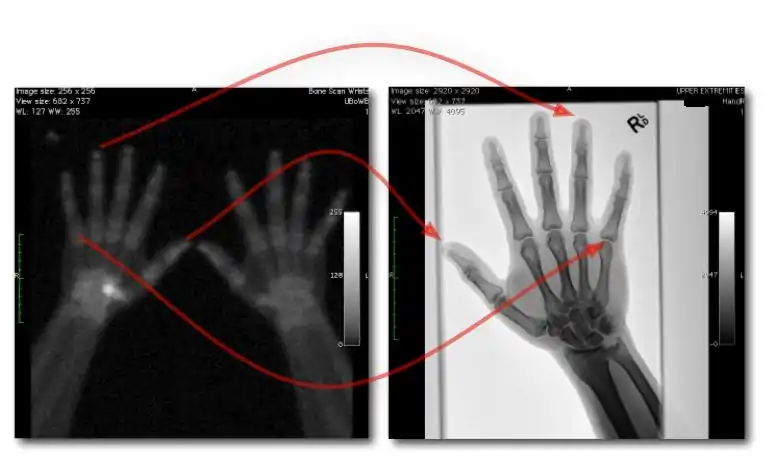

- ↑ Mettler FA Jr, Huda W, Yoshizumi TT & Mahesh M, 2008. Effective doses in radiology and diagnostic nuclear medicine: A catalog. Radiology, 248:254-63.